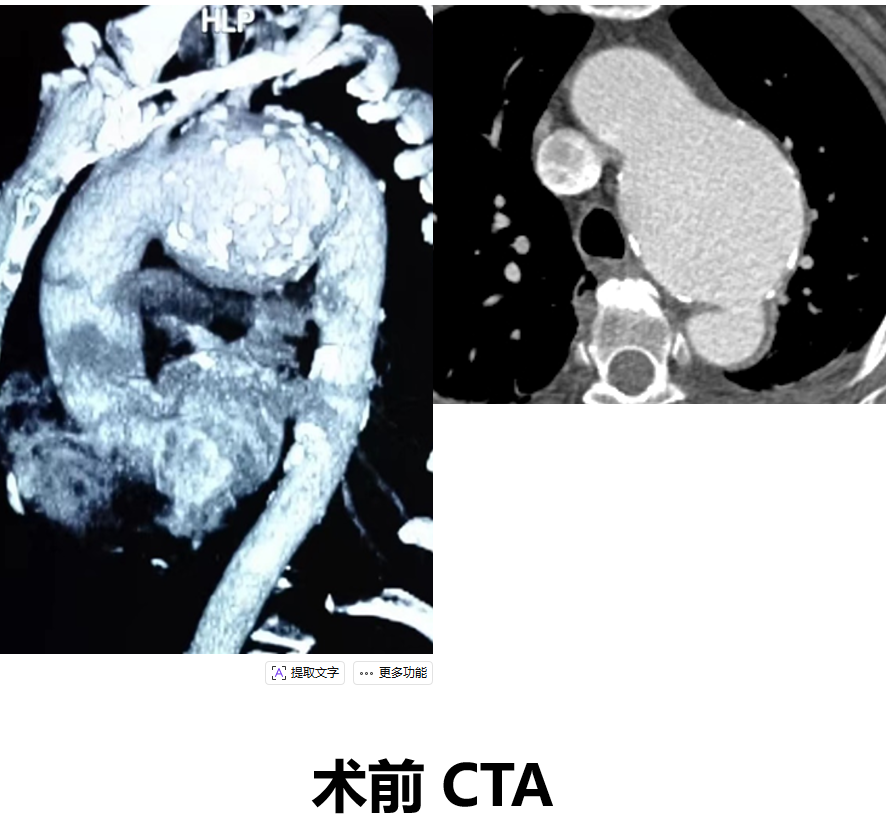

韩某,男,53岁,“查体发现主动脉弓部溃疡15天”入院,主动脉CTA提示:主动脉溃疡(弓部);2. 主动脉壁内血肿。患者高血压病史8年,最高210/130mmHg,无规律服药。

术前 CTA

术前CTA